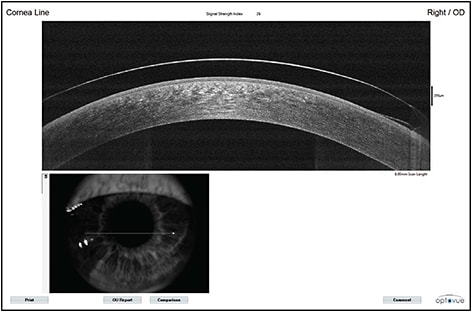

Figure 2a. Anterior segment photography of a well-fit Duette HD lens on a normal cornea. Note the proper centration denoted by the position of the junction.

Figure 2b. Anterior segment OCT of a well-fit Duette HD lens on a normal cornea. The lens is fit “on K,” so an alignment fitting is expected, with edge lift at the junction between GP and soft SiHy skirt.